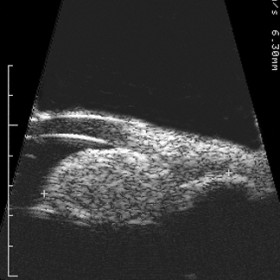

Choroidal hemangioma

Choroidal Hemangioma- 10 MHz B-scan of a circumscribed choroidal hemangioma reveals the hyperechoic - highly reflective tumor